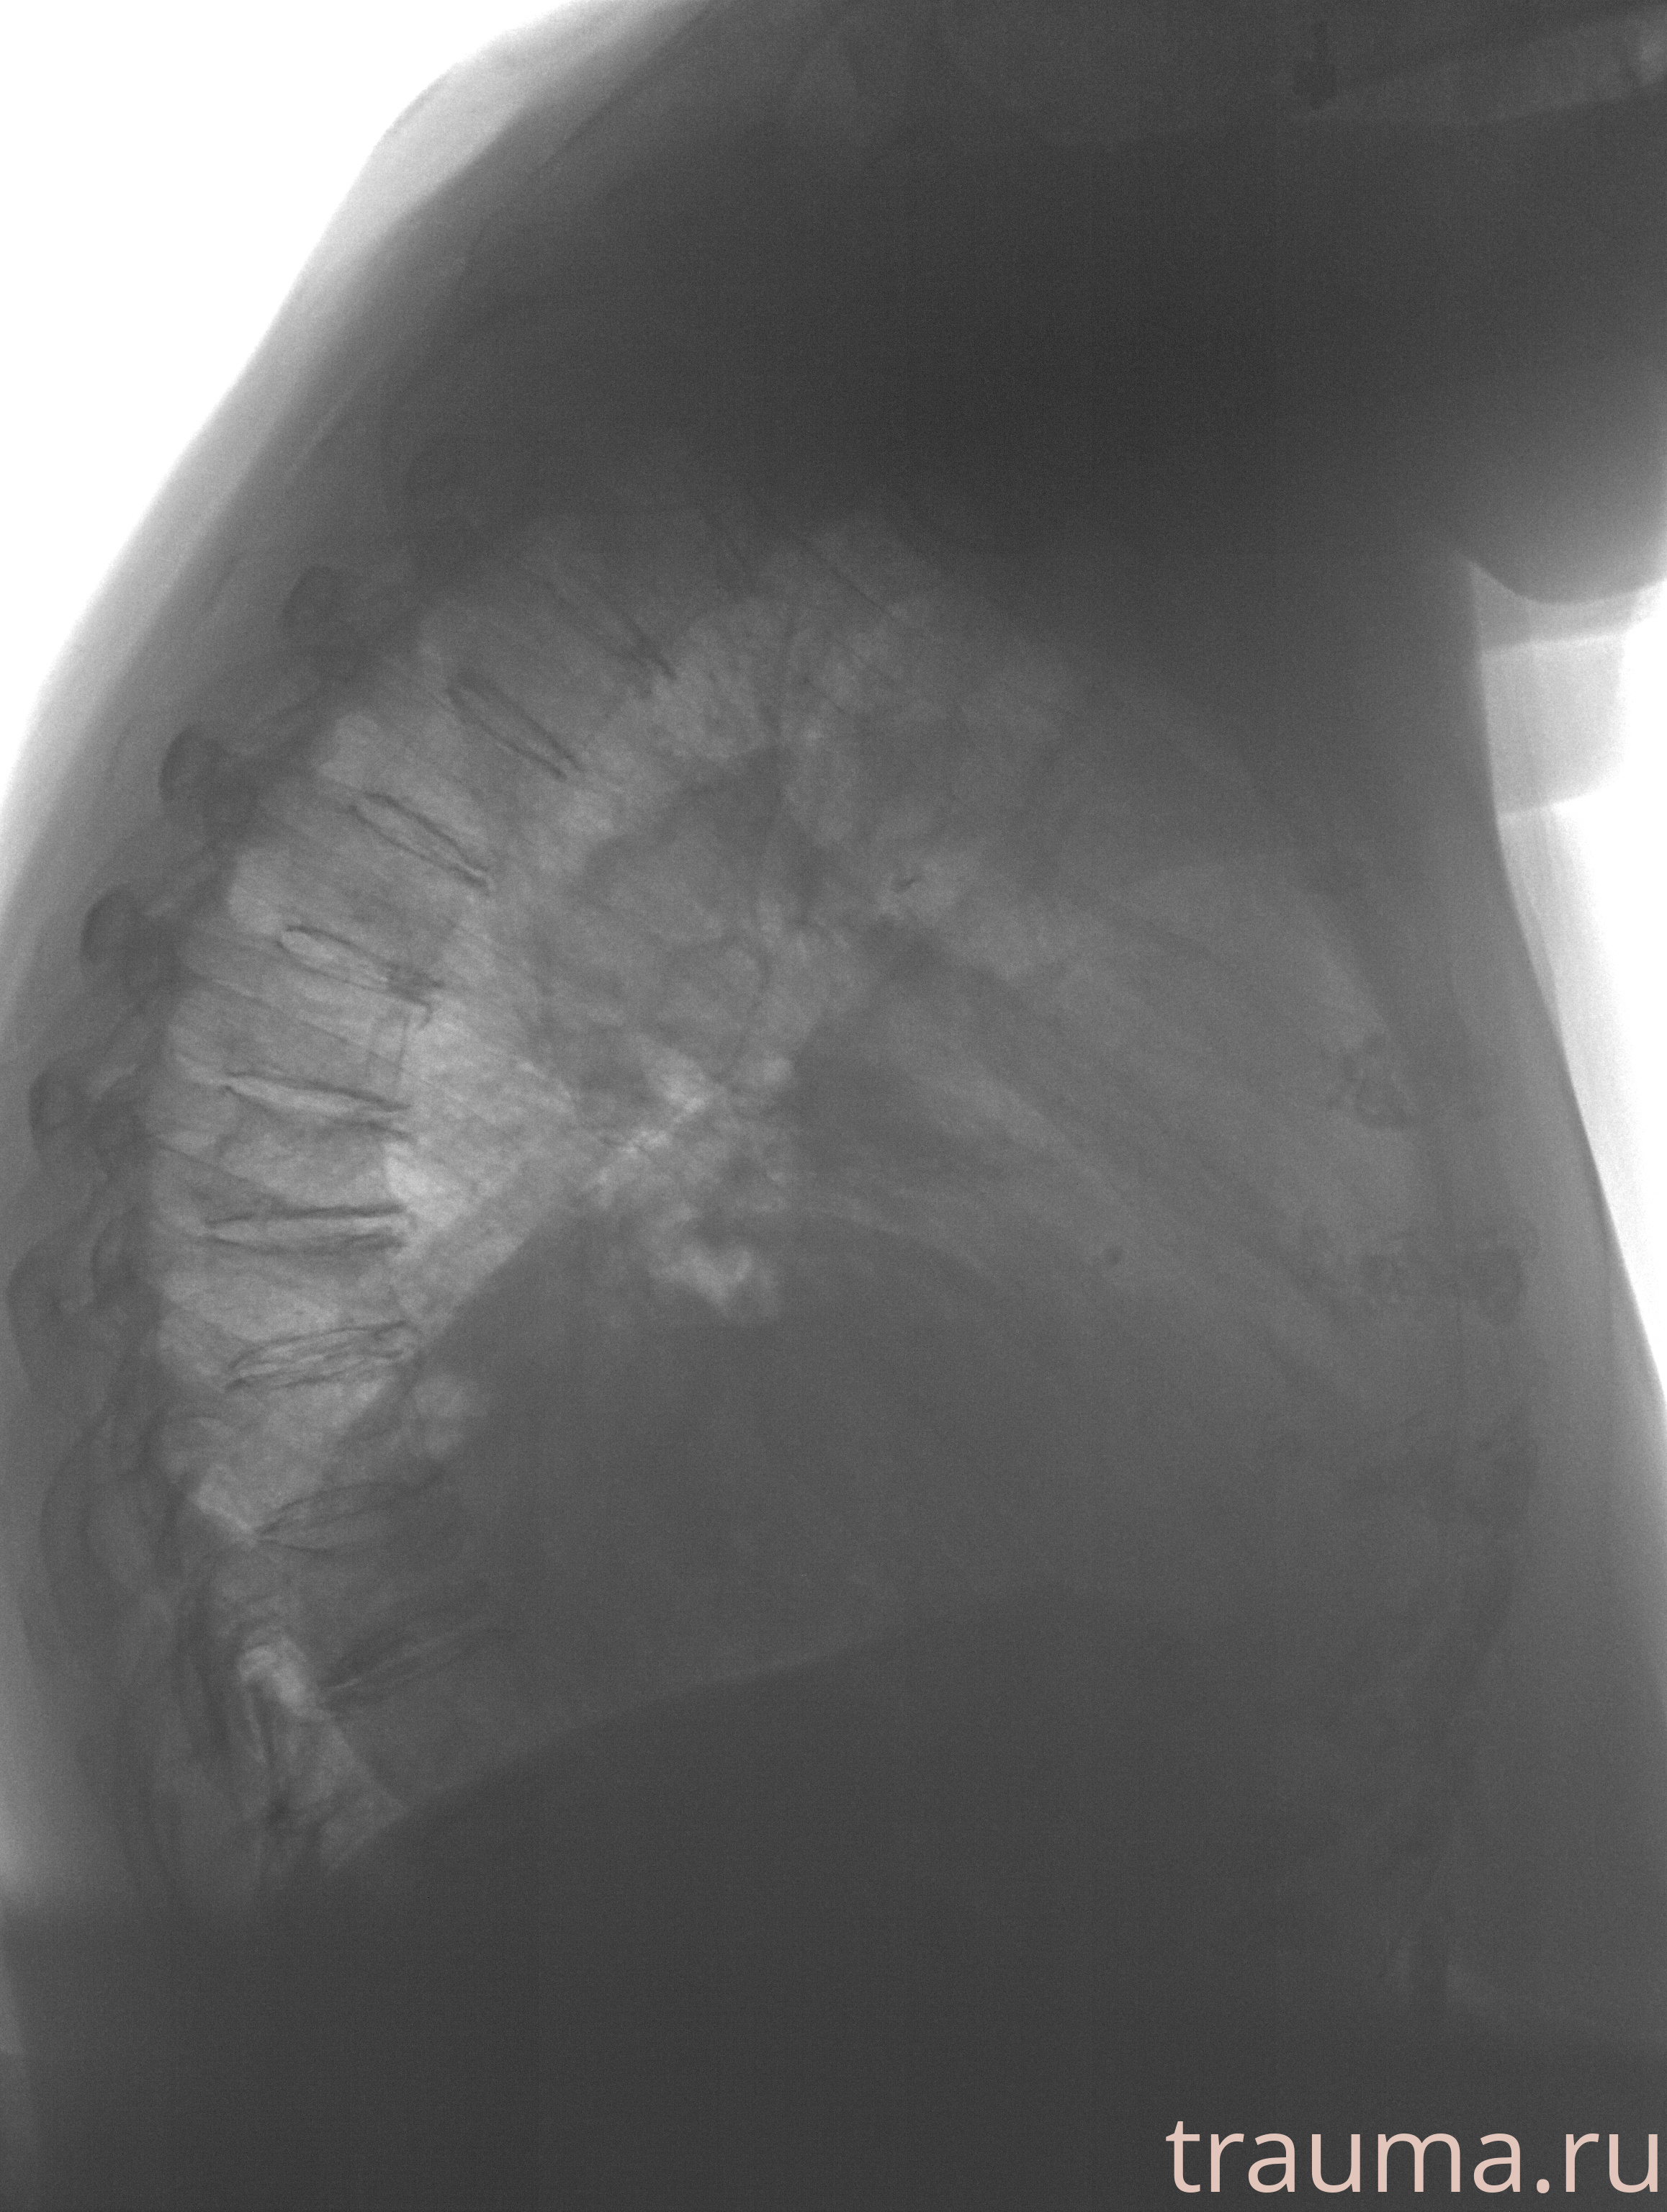

Рентгенограммы

Рентген на дому: по вашему адресу приезжает врач-рентгенолог, травматолог-ортопед с мобильным рентгеновским аппаратом, проводит диагностику травмы или заболевания, делает необходимые рентгенограммы, дает рекомендации по дальнейшему лечению. Получить качественные снимки в домашних условиях возможно благодаря уникальной методике, разработанной МосРентген Центром для института  Склифосовского

при переломе шейки бедра и пневмонии от компании МосРентген Центр - партнера Института имени Склифосовского